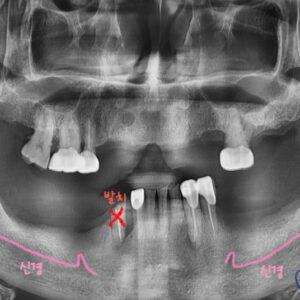

임플란트 전후 사진입니다.

6개월 간의 리콜 체크를 통해

건강하게 임플란트 사용중이십니다.